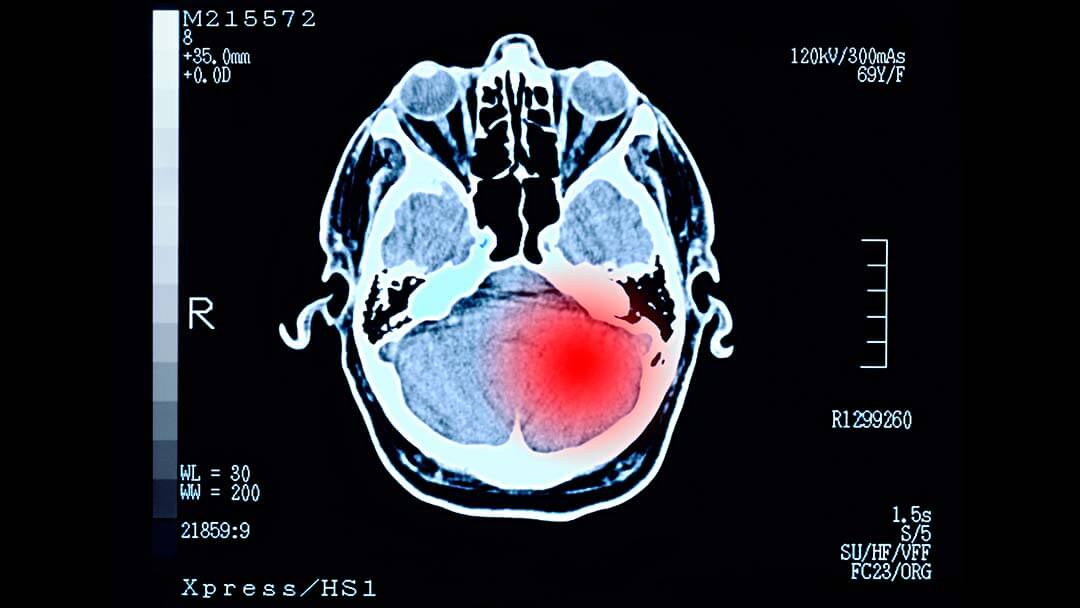

• Conditions Being Studied: Cancer - Brain and Nervous System

The purpose of this study is to evaluate multiple investigational treatments for either newly diagnosed or recurrent glioblastoma to determine if any of these investigational treatments(s) improve how long patients live (overall survival) as compared to standard treatments. The study design allows multiple therapies and combinations of therapies to be screened simultaneously and over time.

Patients 18 years or older who have been newly diagnosed with glioblastoma (GBM) or recurrent GBM may be eligible to participate in the study.